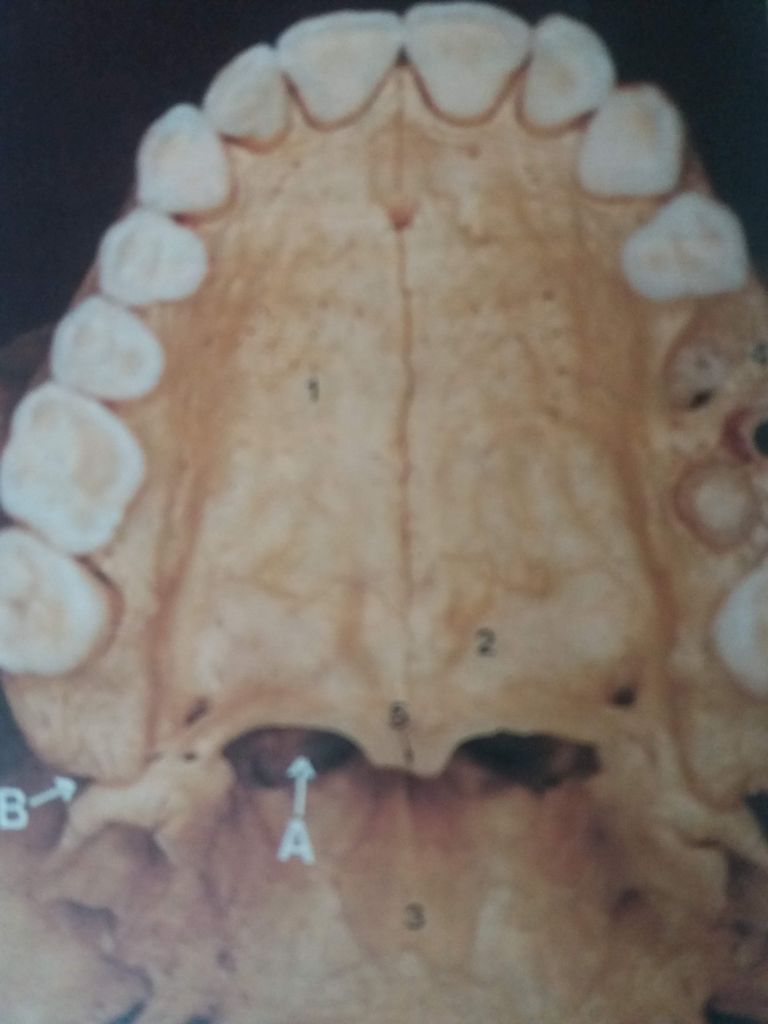

La cavitat bucal és la porció interna de la boca delimitada externament i pel davant pels arcs dentals, per la part posterior comunica amb la faringe. A la part superior hi trobem la volta del paladar i, a la part inferior, el sòl de la boca. Vegeu figura:

La volta del paladar forma la paret superior de la cavitat bucal i s’hi distingeixen dues parts: el paladar dur o volta del paladar, que ocupa els dos terços anteriors, i el paladar tou o vel del paladar, que ocupa el terç posterior.

- El paladar dur està constituït per les apòfisis palatines de l’os maxil·lar superior i per la porció horitzontal de l’os palatí. Aquesta estructura separa la cavitat bucal de les fosses nasals. Aquestes estructures òssies estan recobertes per mucosa que presenta plecs horitzontals més marcats en la part anterior que permeten allotjar les glàndules salivals palatines que es troben entre la mucosa i l’estructura òssia.

- El paladar tou es disposa a continuació del paladar dur. És la porció mòbil del paladar i està format fonamentalment per musculatura recoberta de mucosa, i també entre la musculatura i la mucosa s’hi allotgen glàndules salivals palatines. En la part posterior es perllonga a l’úvula i als costats pels pilars del vel del paladar. En aquests pilars del vel del paladar hi ha unes depressions on s’allotgen les amígdales palatines dreta i esquerra que són de teixit limfoide.